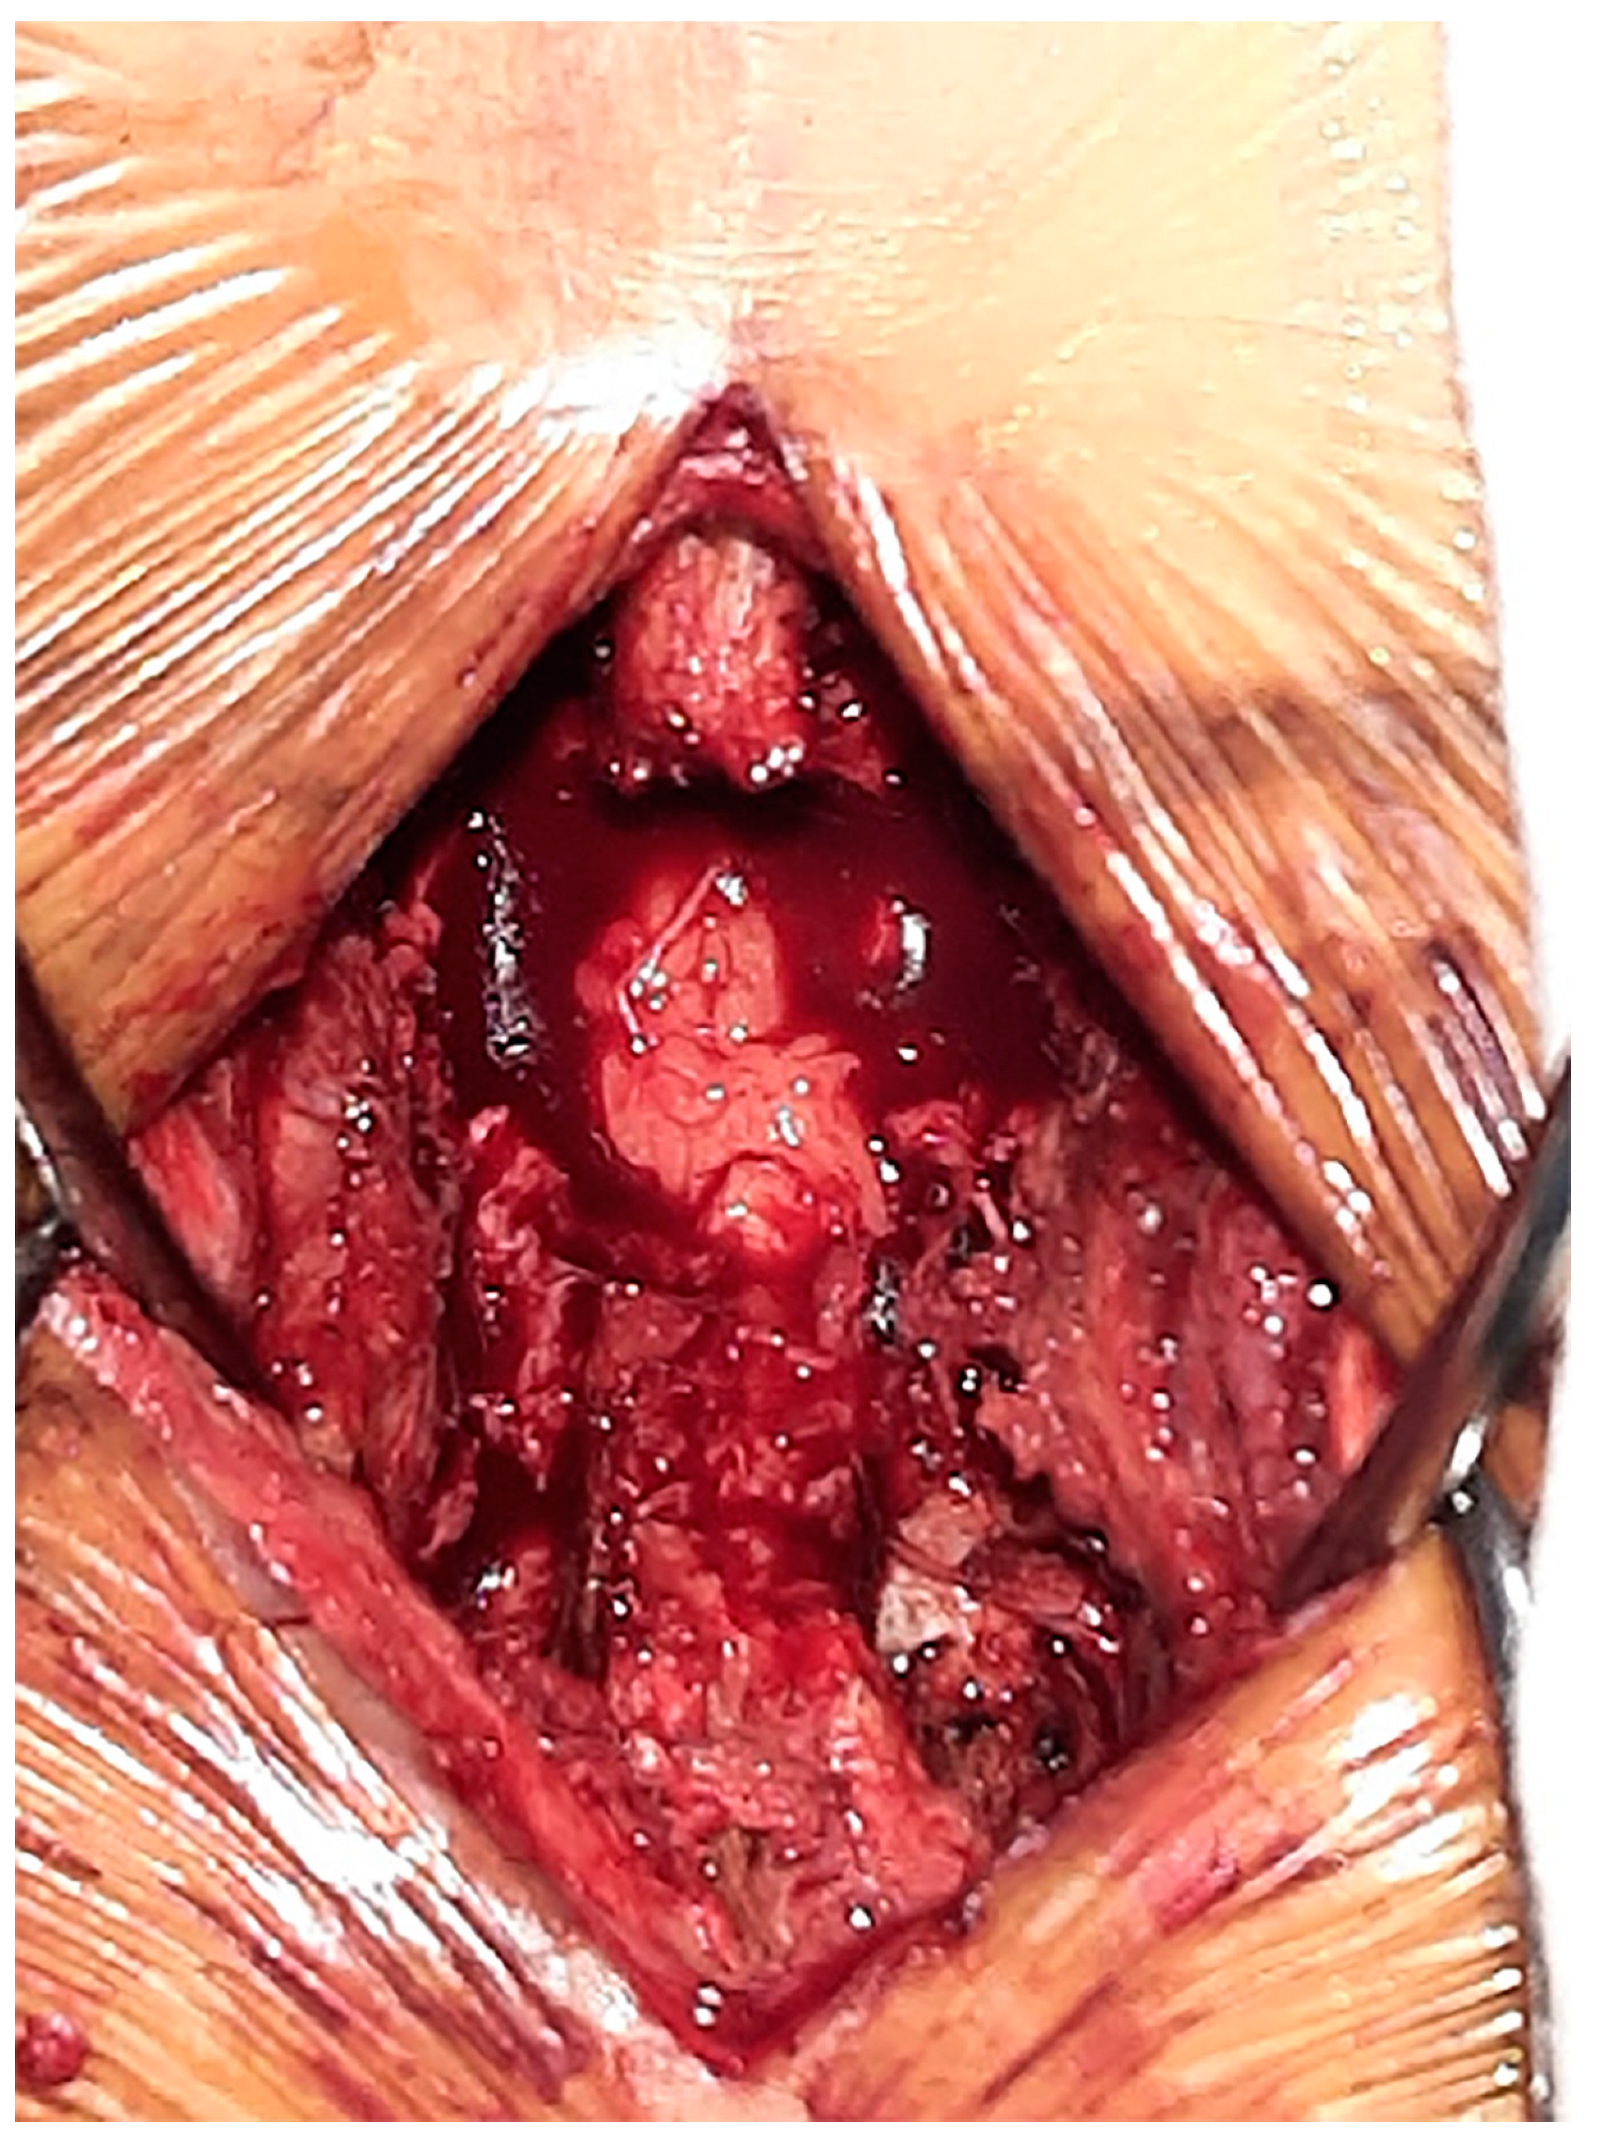

2.1. Case 1

2.2. Case 2